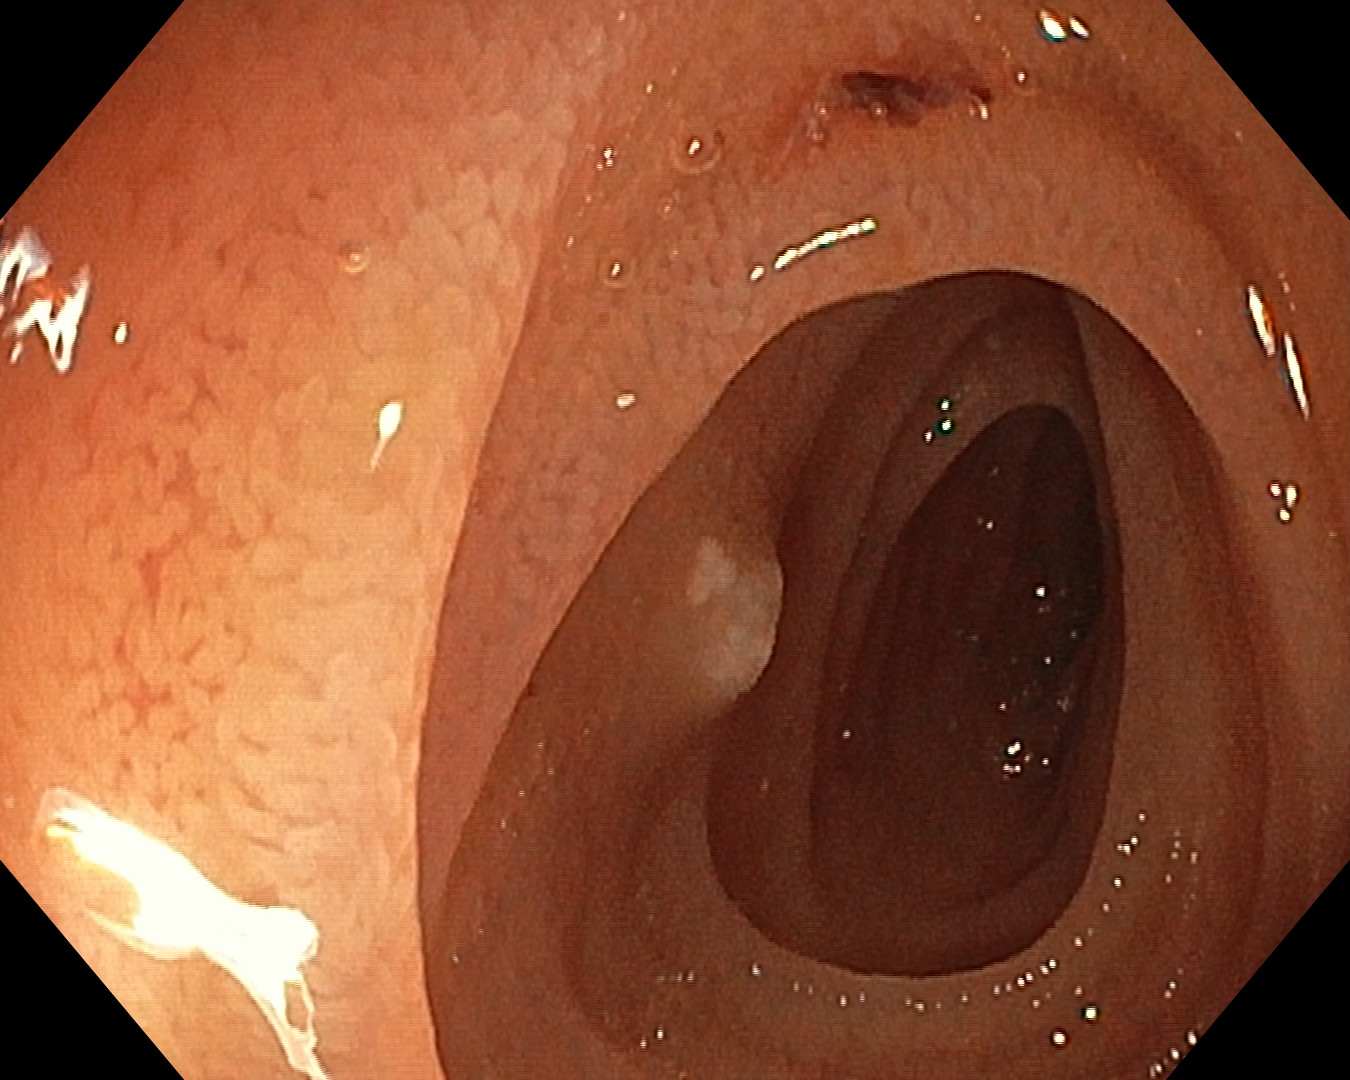

Enteroscopia spirală motorizată poate fi efectuată retrograd, abord mai simplu, fiind asemănător cu o colonoscopie. Adică, aparatul este introdus în organism prin orificiul și canalul anal. Investigația necesită o pregătire anterioară de o zi și se face cu o sedare ușoară. Există însă și abordarea anterograda, cu anestezie generală, care impune prezența unui medic de terapie intensivă, aparatul fiind introdus prin gură”, mai Christian Banciu.